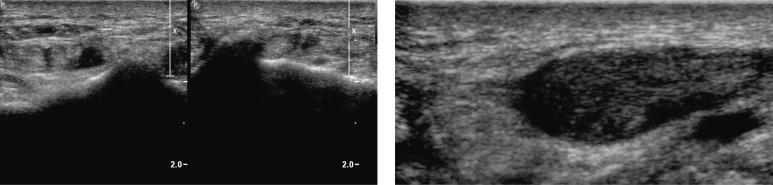

Ultrasound examination is becoming more and more common in patients with rheumatoid diseases. Above all, it enables the assessment of articular soft tissues and constitutes a non-invasive examination. In a rheumatologist's everyday practice, it is conducted at the stage of initial diagnosis as well as to monitor the treatment and to confirm the remission if the clinical picture is ambiguous. The first sign of arthritis (including rheumatoid arthritis) that is visible on ultrasound examination is the thickening of the synovial membrane of the joint cavities, tendon sheaths or bursae. It is frequently accompanied by the exudate in the joint, sheath or bursa. In a subsequent stage, in Doppler examination, enhanced vascularization of the synovial membrane is observed. Sometimes, the inflammatory process of the tendon sheaths also affects the tendons, which might lead to their damage. Moreover, ultrasound examination also reveals erosions and inflammatory cysts (geodes) which attest to the advancement of the disease. A dynamic ultrasound examination enables to diagnose the capsule-ligamentous contracture of the interphalangeal joints, which occurs due to the lack of rehabilitation that should begin at the moment of the commencement of the inflammation. The ultrasound image does not allow for the differentiation between various rheumatoid entities, including those encompassing the joints in the hand, wrist. The observed changes, i.e. thickening of the synovial membrane, hyperemia, effusions, erosions or tendon damage, may accompany various rheumatoid entities. The purpose of the ultrasound examination is to recognize these irregularities, determine their localization and advancement and, finally, to monitor the course of treatment. Furthermore, ultrasound scan enables to assess the joints and tendons in a dynamic examination in relation to local ailments of the patient as well as to monitor the biopsy, aspiration and medicine administration. Sonography is used for a US-guided administration of radioisotope substances for synoviorthesis.

超声检查在类风湿疾病患者中越来越普遍。最重要的是,它能够评估关节软组织,是一种非侵入性检查。在风湿病学家的日常实践中,它在初始诊断阶段进行,也用于监测治疗情况以及在临床表现不明确时确认病情缓解。超声检查可见的关节炎(包括类风湿关节炎)的首个迹象是关节腔、腱鞘或滑囊的滑膜增厚。其常伴有关节、腱鞘或滑囊内积液。在随后阶段,多普勒检查可观察到滑膜血管增多。有时,腱鞘的炎症过程也会影响肌腱,并可能导致肌腱损伤。此外,超声检查还可发现糜烂和炎性囊肿(腱鞘囊肿),这证明疾病在进展。动态超声检查能够诊断指间关节的关节囊韧带挛缩,这是由于在炎症开始时未进行应有的康复治疗所致。超声图像无法区分各种类风湿疾病实体,包括累及手部、腕部关节的疾病。观察到的变化,即滑膜增厚、充血、积液、糜烂或肌腱损伤,可能出现在各种类风湿疾病实体中。超声检查的目的是识别这些异常情况,确定其位置和进展情况,最终监测治疗过程。此外,超声扫描能够在动态检查中评估关节和肌腱与患者局部疾病的关系,还能监测活检、穿刺抽吸和药物给药情况。超声检查用于在超声引导下注射放射性同位素物质进行滑膜切除术。